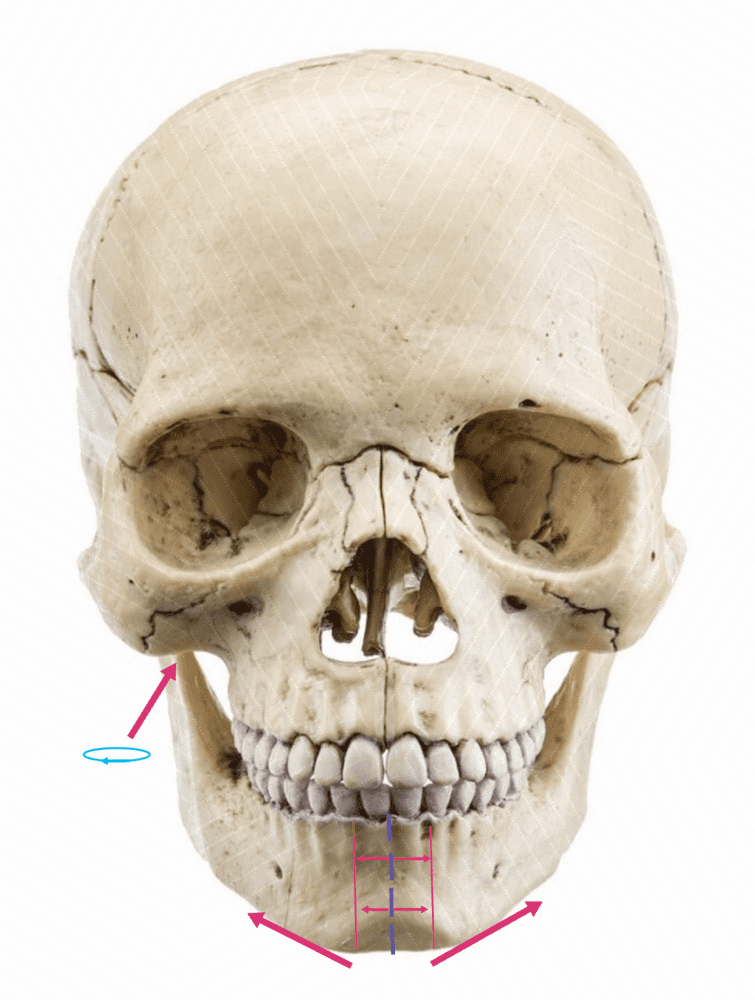

Expands the width of maxilla, mouth, nasal base, and zygomatics expansion. You would need corticopuncture done so you can expand with MSDO at the same rate.

MSDO expands the lower jaw (particularly chin). The lower jaw can follow only so much the forced expansion the maxilla is subjected to from the MSE. This, in combination with the MSE can widen the chin, expand the palate, increase the lateral protrusion of the zygos

Expands the width of maxilla, mouth, nasal base, and zygomatics expansion. You would need corticopuncture done so you can expand with MSDO at the same rate.

MSE Results (Cheekbones width, maxilla).

10mm of MSE equals =

8.4 mm - cheekbones width (0.84mm gain for every milimeter of MSE expansion)

1.2 mm - Maxilla forward growth (upper and lower)

10mm of MSE equals =

8.4 mm - cheekbones width (0.84mm gain for every milimeter of MSE expansion)

1.2 mm - Maxilla forward growth (upper and lower)

MSDO expands the lower jaw (particularly chin). The lower jaw can follow only so much the forced expansion the maxilla is subjected to from the MSE. This, in combination with the MSE can widen the chin, expand the palate, increase the lateral protrusion of the zygos